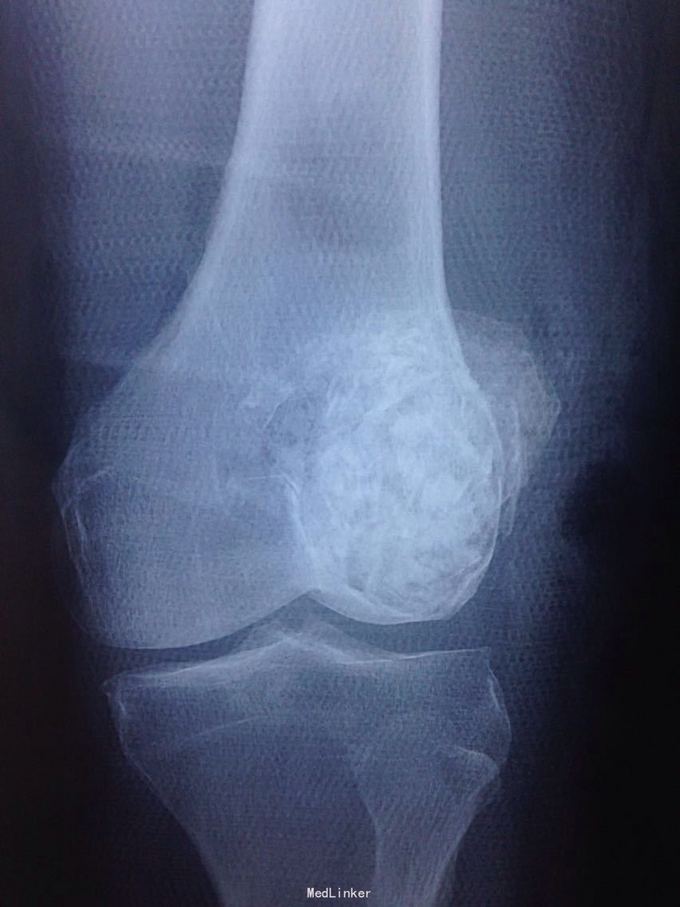

男性51岁,左膝关节疼痛不适10余年。因症状较轻,不影响活动,未曾系统诊治。一月前因扭伤致疼痛加重,拍片检查,见股骨远端骨质异常,进一步行CT示股骨髁占位病变,考虑骨囊肿。既往有高血压,糖尿病病史。近期无低热,体重下降。

左膝关节外观皮色正常,无明显肿胀,屈伸活动未见明显受限,外髁轻度压痛,侧方应力及抽屉试验阴性,半月板回旋挤压试验阴性,浮髌试验阴性。肢端感觉,血运正常。

诊断:左股骨远端占位 因皮质完整,行手术开窗刮除,自体髂骨及同种异体骨混合植骨填充治疗。切取组织送病理检查

刮除占位组织如图所示,送病理检查了,结果还没回来。 没有全身症状,像是原发灶,骨皮质完整,没有明显骨膜反应请专家们看看,什么可能性比较大? 补上病理结果和术后片子